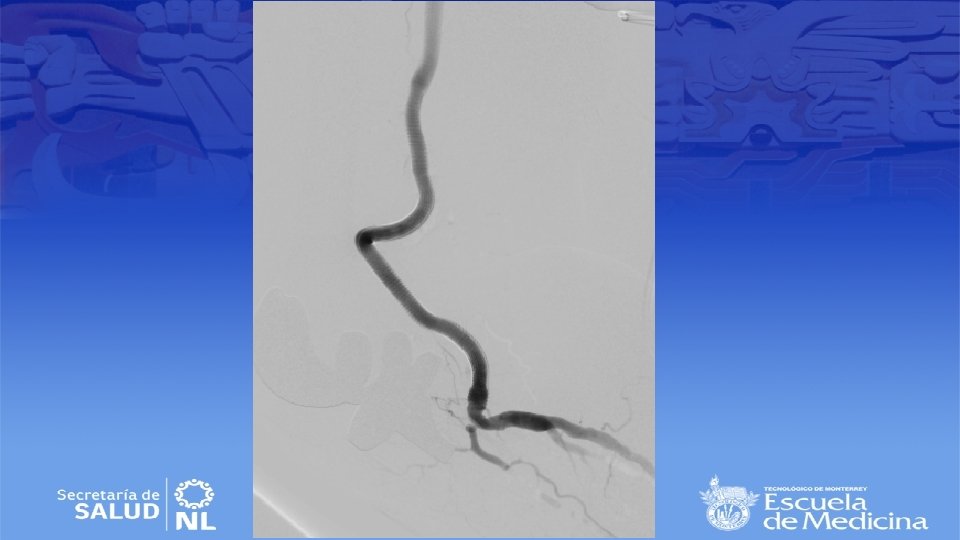

Angiotac

Diagnostico • Ultrasonido Doppler, Angiotac, angioresonancia • Arteriografía es mas apropiada para sintomatología aguda

Cirugía de emergencia • Establecer viabilidad de la extremidad (buscar deficiencia motora o sensitiva) • Sin daño se inicia anticoagulación sistémica y se realiza angiografía en busca de algún vaso viable para bypass. • Si no se encuentran se realiza trombolisis dirigida • Si se encuentra daño el bypass sigue siendo el mejor tratamiento • Si no hay vaso viable se realizara trombectomía tibial

Cirugía endovascular • Para pacientes con alto riesgo quirúrgico • Deben de tener al menos 2 cm de arteria proximal y distal sin patología para anclar la endoprótesis • Se repite la angiografía durante el procedimiento para selección de la endoprótesis correcta • Debe de ser 10 a 15% mas grande que el diámetro del vaso